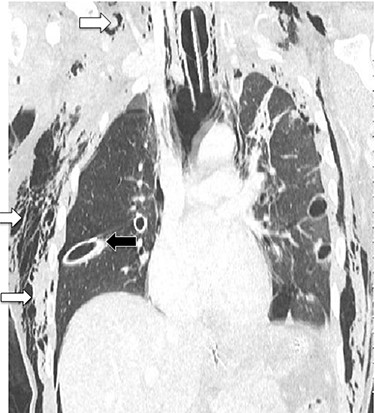

CT chest showing chest tubes in situ (black arrow) and soft tissue emphysema (white arrows).

A 29-year-old male presented to the Trauma Unit, after being hit by a car. Because of desaturation, diminished air entry bilaterally and subcutaneous emphysema, he was intubated, and bilateral chest tubes were placed. After stabilization, a pan-CT scan revealed extensive soft tissue emphysema in the neck and chest, as well as pneumomediastinum. An additional two chest tubes were placed bilaterally because of incomplete lung expansion (Fig. 1). The patient improved over several days and was eventually discharged home in stable condition.